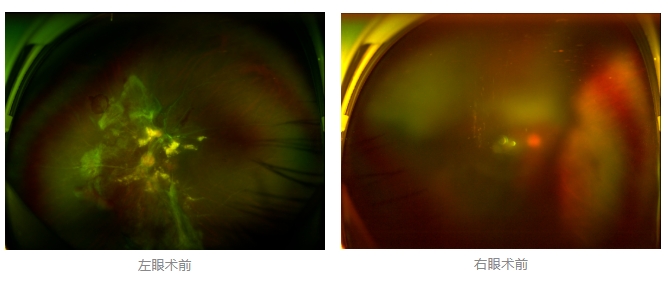

經(jīng)廈門眼科中心眼底病??菩姓魅瓮鯐圆z查后,確診其雙眼糖尿病視網(wǎng)膜病變VI期,伴發(fā)雙眼視網(wǎng)膜脫離和黃斑水腫,且右眼視網(wǎng)膜上增殖膜叢生,若再不盡快進(jìn)行治療,恐有失明風(fēng)險(xiǎn)。

面對(duì)陳先生的復(fù)雜病情,王曉波主任采用玻璃體切割術(shù)聯(lián)合膜切除術(shù)等方式,精細(xì)剝離牽拉視網(wǎng)膜的增殖膜,復(fù)位脫離的視網(wǎng)膜,同時(shí)進(jìn)行玻璃體腔注藥促進(jìn)黃斑水腫吸收。

經(jīng)過(guò)規(guī)范化治療,術(shù)后2個(gè)月復(fù)查時(shí)陳先生的視力已有明顯改善,矯正視力從眼前指數(shù)提升至0.3,成功擺脫“失明危機(jī)”。但王曉波主任強(qiáng)調(diào):“這只是階段性勝利,后續(xù)治療不能松懈。”